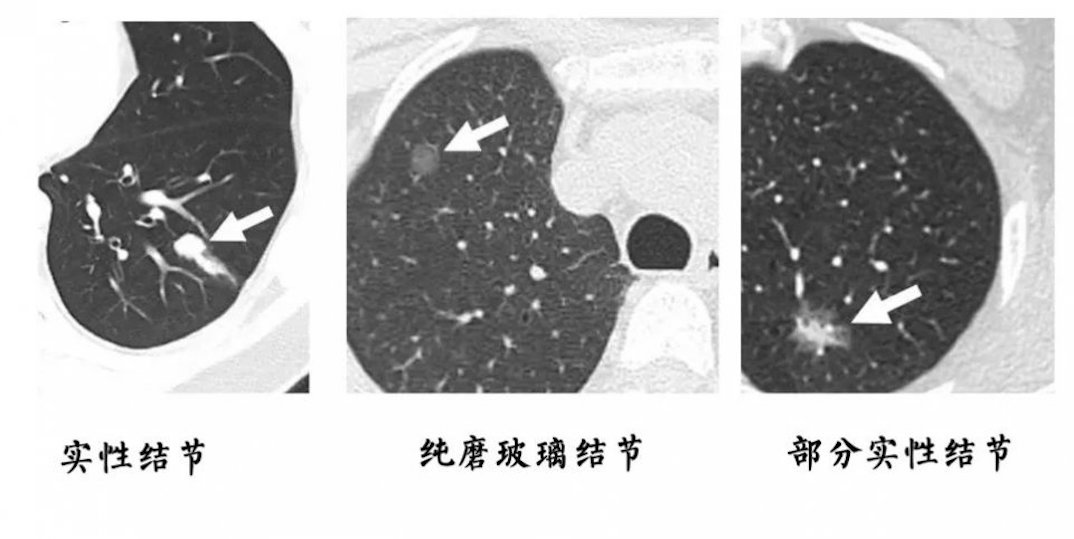

胸部CT上发现的磨玻璃样结节(箭头所示),病理结果为微浸润性腺癌(早期的肺癌),这在胸片上根本看不到。

胸部CT是胸部查体的首选检查。

胸部CT由于其分辨率高,可以发现肺上很小的结节灶,因此胸部CT对于肺癌的早期诊断具有极其重要的价值。而鉴于胸部CT有放射性,遂提出了低剂量胸部CT的概念。

医学上把直径小于或等于3cm的圆形或类圆形病灶称为结节,直径大于3cm的病灶通常用“肿块”一词。

而对于直径小于1cm的,我们称之为小结节。

直径大于1cm的,我们称之为大结节。

直径越大,其恶性的可能性则越大。